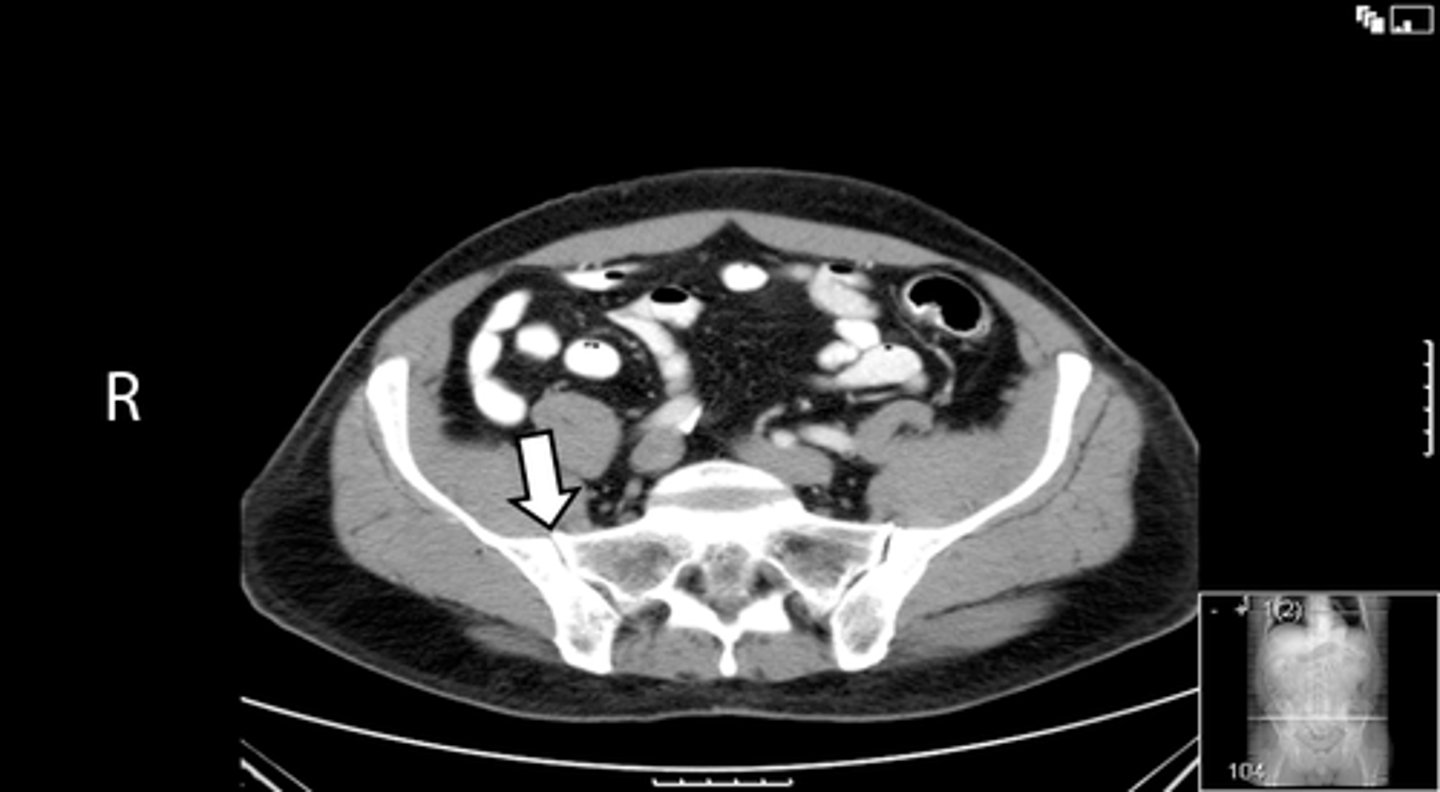

Axial bony pelvis CT

What is the image?

L ilium

What is indicated in the image?

L sacroiliac joint

R ilium

R sacroiliac joint

Sacrum

L acetabulum

L femoral head

L piriformis muscle

R femoral head

R piriformis muscle

R acetabulum (posterior part)